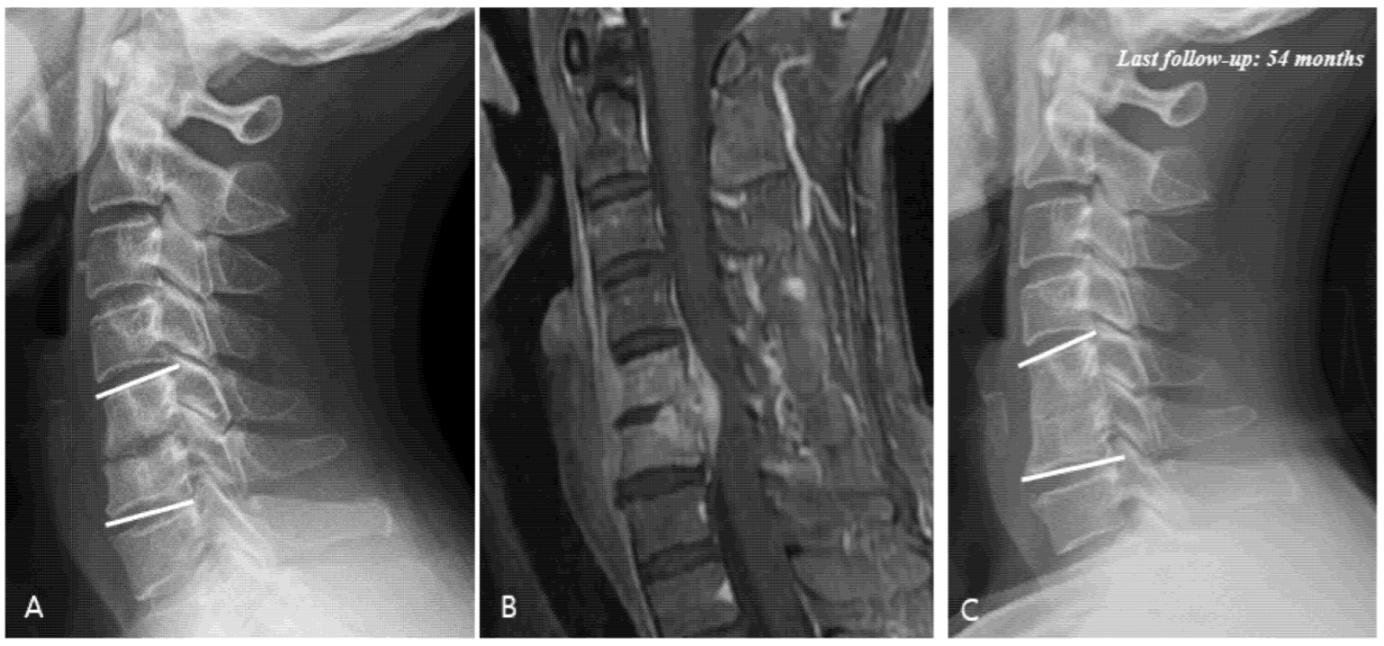

Figure 2. (A) Simple radiographs of 51-year-old male showing C5–C6 disc space narrowing and osteolytic change. (B) Gadolinium-enhanced magnetic resonance image showing infectious spondylodiscitis at C5–C6 accompanied by prevertebral abscess and anterior epidural abscess. (C) Last follow-up (54 months) plain radiographs showing fusion state after antibiotic treatment.

The results of the radiological analysis are summarized in Table 5. The C5–C6 segment was the most commonly involved site in the entire study population (47.5%). It was also the most common site of occurrence in each group stratified according to the period. The C1-C2 segment was the least-affected site (1.7%). MRI revealed that the infection was located in the anterior spinal cord in all groups, except for three patients (two patients: posterior, one patient: anterior and posterior) (total: 94.9%, group A: 100%, group B: 92.3%, and group C: 94.6%). Epidural abscess formation was observed in 24 patients (40.7%) on their MRI (Figure 2). An epidural abscess was absent in group A but increased to 3 patients (23.1%) in group B and 21 patients (56.8%) in group C. Twenty patients (33.9%) had a multisegmental infection, and its frequency of distribution was as follows: 1 patient (11.1%) in group A, which increased to 2 patients (15.4%) in group B and 17 patients (45.9%) in group C. The incidence of epidural abscess formation and multisegmental infection rose significantly in recent years (epidural abscess: p = 0.001, multisegmental infection: p = 0.017).